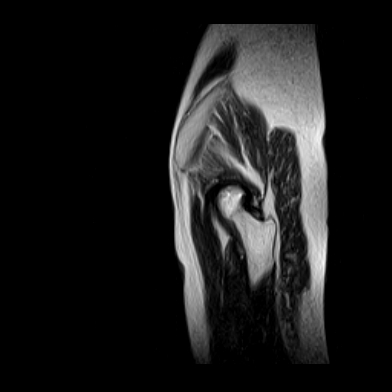

请看看我的片子,我得的什么病,该怎么治疗?谢谢[img][/img]

片子不全,应该是左侧股骨头无菌坏死,右侧似乎没问题,到正规医院治疗,千万别看广告去小医院,吃中药什么的,都是骗人的(说了也白说,百分百都得让人骗点钱才甘心。)

应该是左侧股骨头无菌坏死